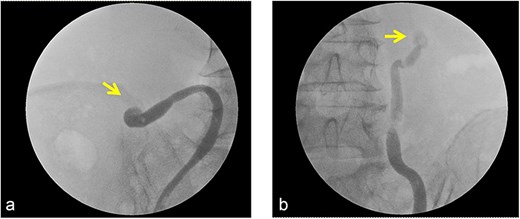

Transthoracic echocardiography showed severe left ventricular systolic dysfunction with a left ventricular ejection fraction (LVEF) of 24% by Simpson’s method (Fig. 2a). Kidney–ureter–bladder radiography and computed tomography performed to investigate systemic causes revealed severe bilateral hydronephrosis due to bilateral impacted ureteral stones (left: 17 × 7 mm; right: 10 × 8 mm; attenuation ~1350 HU) (Fig. 3). Retrograde ureteral stent placement was attempted on the same day but failed because contrast medium could not pass through the obstructed segments (Fig. 4). A left percutaneous nephrostomy (PCN) was therefore performed, followed by right PCN one week later. Concomitantly, guideline-directed heart failure therapy was initiated, including spironolactone (12.5 mg/day), empagliflozin (10 mg/day), sacubitril/valsartan (100 mg/day), and bisoprolol fumarate (1.25 mg/day).

Intraoperative findings during attempted ureteral stenting. Retrograde pyelography demonstrated no passage of contrast agent across the site of the impacted ureteral stone, rendering ureteral stent placement unsuccessful.